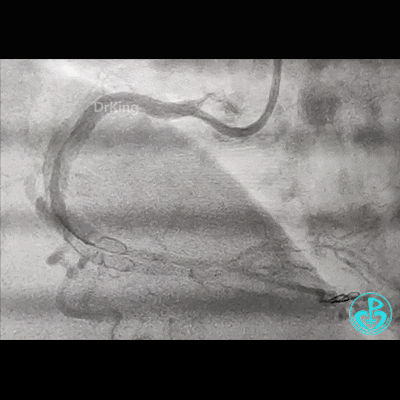

冠脉造影

右锁骨下动脉迂曲打圈,影像如下:

病变简单吧!